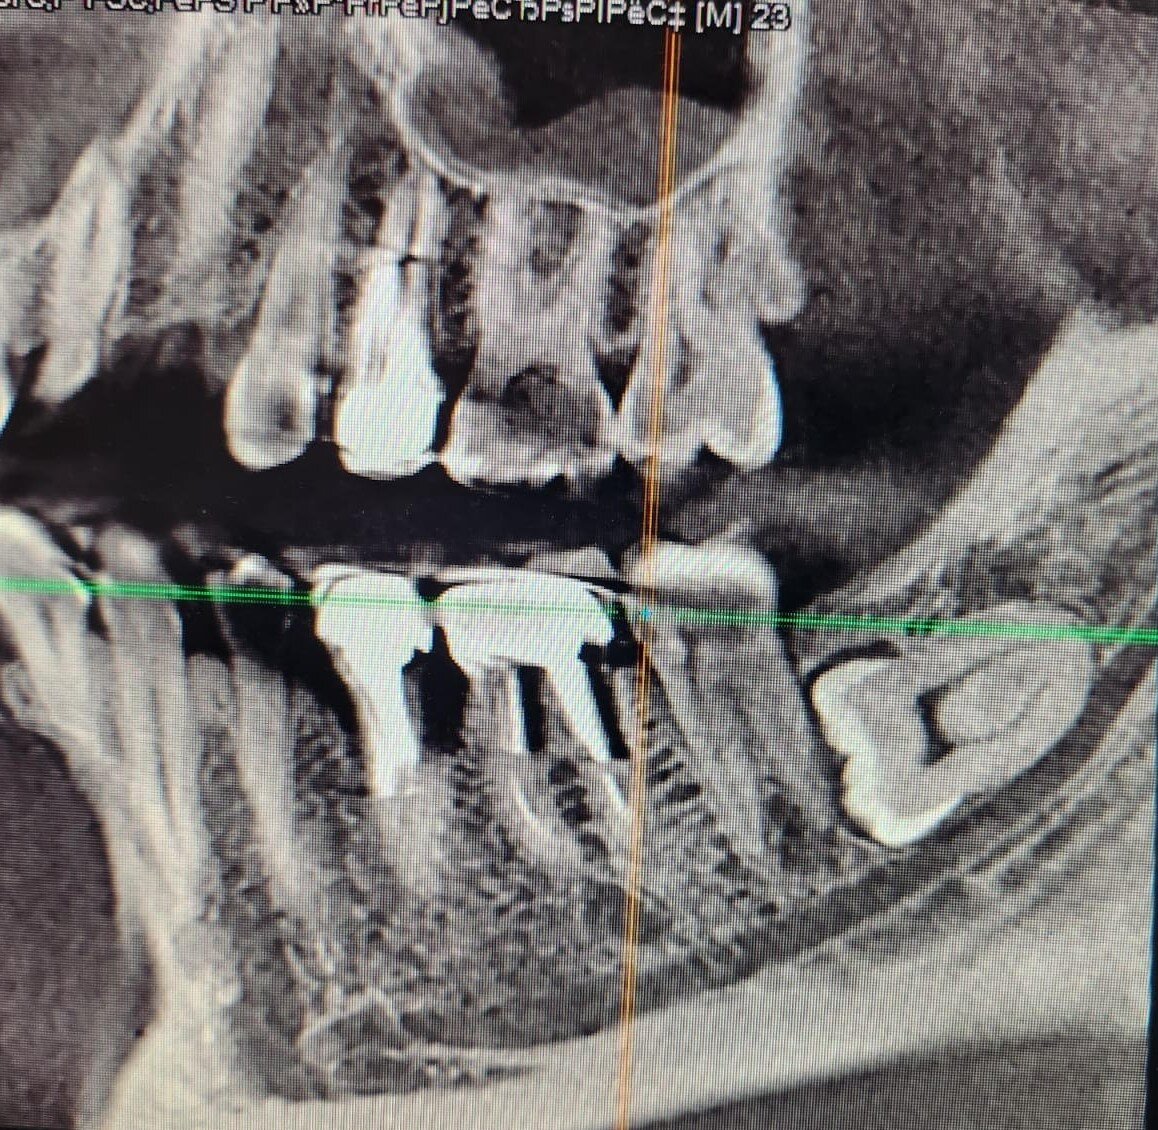

Итак, около недели тому назад сижу на работе, беды не чую. Ассистент готовит кабинет к приёму очередного пациента. На почту приходит сообщение от некоего Константина, который с двух попыток в разных нижегородских клиниках не смог избавиться от вот такого зуба мудрости.

Горизонтальный – зуб мудрости, черная полоска под ним – нижнечелюстной нерв.

Казалось бы, – что должно пойти не так при удалении стандартной восьмерки? Если время этого самого удаления занимает 20, а в худшем случае 30 минут. А вот что.